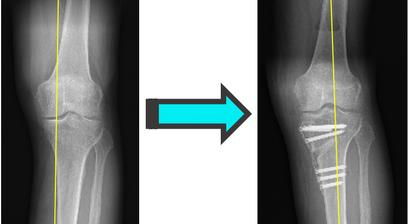

Beinachsenkorrektur / Umstellungsosteotomie

Mein fachärztlicher Schwerpunkt liegt in der Behandlung des Kniegelenks. Durch die internationale Ausbildung an einer Knieklinik, aktive Mitgliedschaft in zahlreichen wissenschaftlichen Fachgesellschaften sowie langjährige Erfahrung führe ich auch komplexe Knieoperationen (u.a. Meniskustransplantation) und Kombinationseingriffe in höchster Fallzahl in Wien durch.